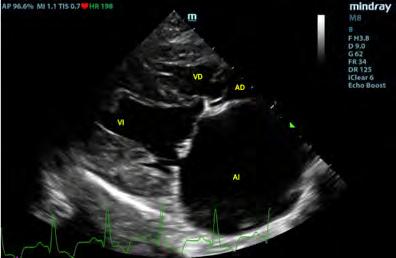

Ecocardiográficamente se observó una dilatación severa del atrio izquierdo (AI) (ratio aorta/atrio izquierdo4 de 3,88; diámetro normalizado del atrio izquierdo5 de 26,91) y dilatación del ventrículo izquierdo (diá-

11

metro interno del ventrículo izquierdo normalizado en diástole6 de 2,28) secundarios a un engrosamiento, fallo de coaptación y prolapso de las valvas de la válvula mitral, determinando una regurgitación mitrálica posterior grave. Se realizó radiología torácica para valorar la presencia de edema pulmonar, observando un patrón intersticial-alveolar severo en el área perihiliar y en los lóbulos caudales pulmonares, compatible con la presencia de edema pulmonar de origen cardiogénico. Tras la realización de la radiografía torácica, se diagnosticó ECDVM en estadio C7 agudo, con una puntuación ecocardiográfica de la insuficiencia mitral (MINE)8 de 12. No se observó derrame pericárdico durante la realización del examen (Figs. 1 y 2).

Posteriormente se evaluó al paciente mediante un examen TFAST, detectando derrame pericárdico y disminución del tamaño del AI (Fig. 4), como hallazgos diferentes a los observados en el examen realizado previo a la radiografía. La rápida respuesta por parte del equipo veterinario implicó que en este primer examen ecográfico tras el desvanecimiento del paciente no se había producido la formación del coágulo para taponar la fisura de la pared, observando flujo desde el AI hacia el saco pericárdico. Se realizaron exámenes TFAST seriados para evaluar la necesidad de realizar una pericardiocentesis al paciente durante la hora si-

Figura 1. Corte paraesternal derecho 4 cámaras, previo a la rotura del atrio izquierdo. VI: ventrículo izquierdo; VD: ventrículo derecho; AI: atrio izquierdo; AD: atrio derecho. Figura 2. Corte paraesternal derecho transversal a la altura del atrio izquierdo y aorta, previo a la rotura del atrio izquierdo. Ao: aorta; AI: atrio izquierdo. Figura 3. Radiografía torácica latero-lateral derecha realizada en el momento que se produjo la rotura del atrio izquierdo. Figura 4. Examen TFAST tras la rotura del atrio izquierdo donde podemos observar un corte transversal del corazón a la altura de los músculos papilares de ventrículo izquierdo. Se puede observar la presencia de derrame pericárdico. VD: ventrículo derecho; VI: ventrículo izquierdo.

guiente al episodio. En los exámenes seriados realizados no se observaron signos ecocardiográficos de taponamiento cardíaco, por lo que se decidió no realizar un vaciado del contenido pericárdico mediante pericardiocentesis9,10 y se optó por un tratamiento de soporte basado en oxigenoterapia y fluidoterapia, buscando mantener un correcto gasto cardíaco sin aumentar en exceso la presión sistólica del paciente, lo que podría producir un aumento del sangrado a través del defecto de la pared atrial, así como una dosis única de pimobendán (Vetmedin, Boehringer Ingelheim, Rhein) por vía intravenosa a 0,15 mg/kg. A los 15 minutos tras el episodio de desvanecimiento, se observó la presencia de una estructura hiperecoica en la pared del AI en el examen ecográfico, compatible con la formación de un coágulo (Fig. 5).

Figura 5. Corte paraesternal derecho 4 cámaras tras la rotura del atrio izquierdo. Se puede observar la formación de una estructura compatible con un coágulo dentro del saco pericárdico. AD: atrio derecho; AI: atrio izquierdo.